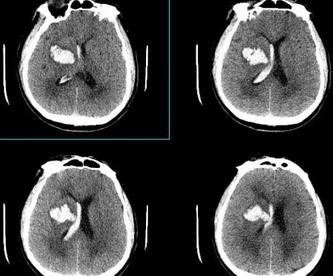

고혈압성 뇌출혈은 뇌혈관이 터져 뇌 조직에 출혈하는 응급 상황입니다. 고혈압 환자에게서 흔히 발생하며, 빠른 진단과 치료가 중요합니다. 치료가 지연되거나 적절하지 않을 경우 사망이나 심각한 장애를 초래할 수 있습니다.

2) 수술

- 뇌종 제거 : 혈종이 크고 뇌압을 높이거나 신경학적 증상을 악화시킬 경우 수술을 통해 혈종을 제거합니다.